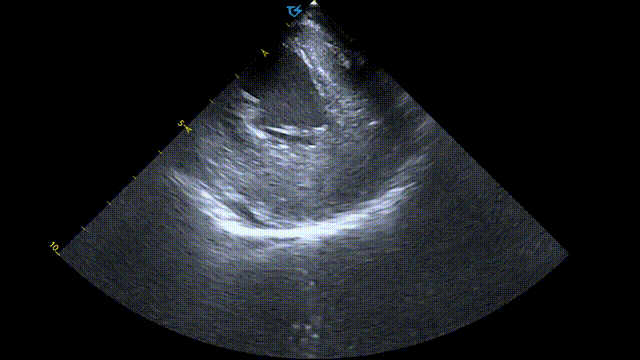

术前术后心包对比:

术前心包基线扫描

术后心包检查

本次手术是在霆升心腔内超声指导下进行的脉冲消融手术。由于ICE提供的是实时且高清的图像,一方面可以清楚直视房间隔的位置,对于房间隔穿刺有很大的优势,另一方面术中医生可以实时观察到脉冲导管在肺静脉口部及前庭贴壁的情况,并且能实时监测到可能的并发症,如心包积液,从而显著减少了对放射线的需求。两者结合后,ICE指导下脉冲电场消融有望引领房颤消融进入新阶段。